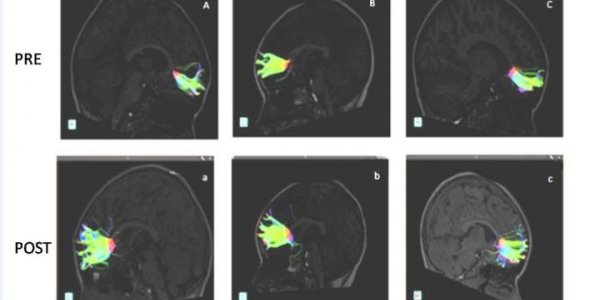

Ko and colleagues said the case provides evidence that, in addition to microcephaly, (a condition marked by an abnormally small head in newborns and widely linked to the Zika outbreak in Brazil), congenital Zika infection may also be linked to hydrops fetalis (abnormal accumulation of fluid in fetal compartments), hydranencephaly (almost complete loss of brain tissue) and fetal demise (stillbirth).

By the 30th week of the pregnancy, the fetus showed a range of birth defects. Labor was induced at the 32nd week. Researchers subsequently confirmed the presence of the Zika virus in the fetus. The strain of Zika that was found appears to be the same strain that is currently spreading elsewhere.